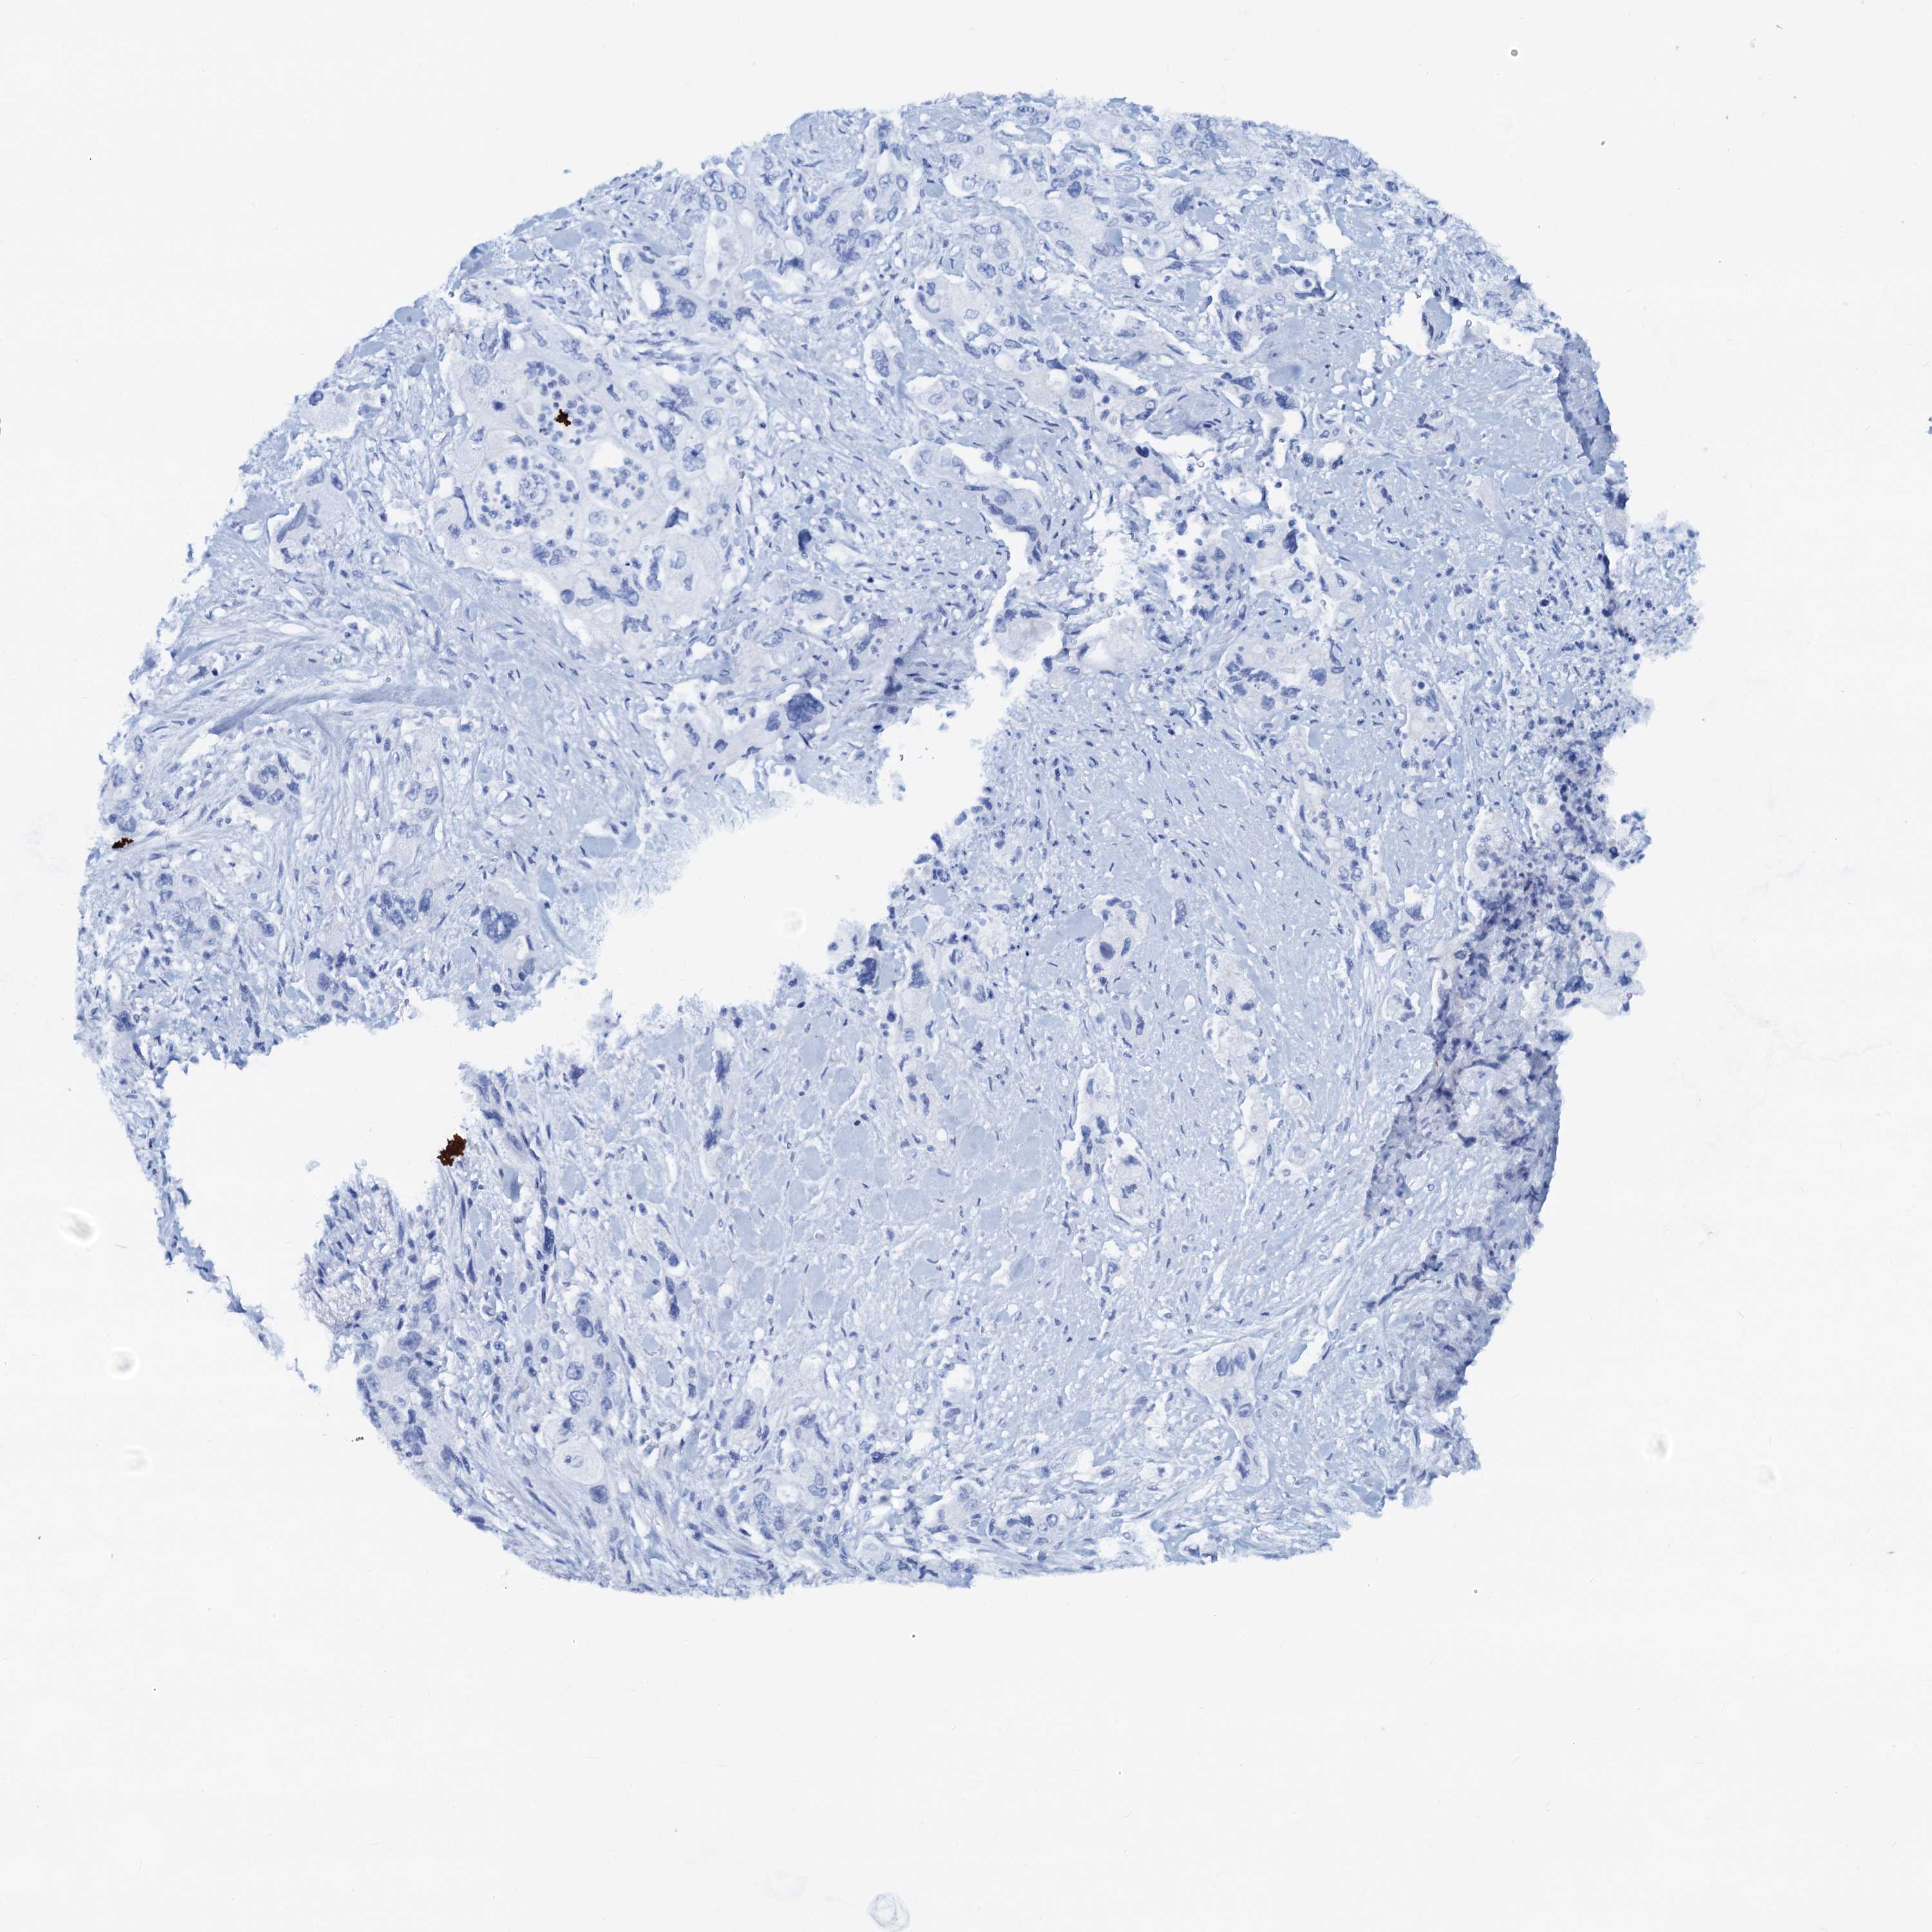

PANCREATIC CANCER - Protein expressioni

A mouse-over function shows sample information and annotation data. Click on an image to view it in a full screen mode. Samples can be filtered based on level of antibody staining by selecting one or several of the following categories: high, medium, low and not detected. The assay and annotation is described here.

Note that samples used for immunohistochemistry by the Human Protein Atlas do not correspond to samples in the TCGA dataset.

Antibody stainingi

Antibody staining in the annotated cell types in the current human tissue is reported as not detected, low, medium, or high, based on conventional immunohistochemistry profiling in selected tissues. This score is based on the combination of the staining intensity and fraction of stained cells.

Each image is clickable and will lead to virtual microscopy that enables deeper exploration of all samples and also displays staining intensity scores, fraction scores and subcellular localization as well as patient and tissue information for each sample.

Antibody HPA038672

Antibody HPA038673

Antibody CAB034319

Staining

High

Medium

Low

Not detected

Intensity

Strong

Moderate

Weak

Negative

Quantity

>75%

75%-25%

<25%

None

Location

Nuclear

Cytoplasmic/membranous

Cytoplasmic/membranous,nuclear

Adenocarcinoma, NOS